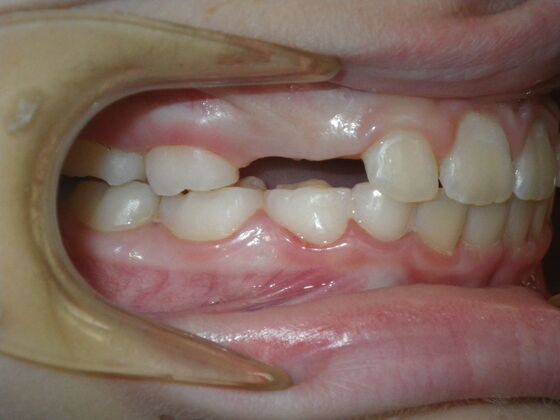

Patient presents with delayed eruption of the upper right central incisor and lower anterior crowding. Treatment plan to include exposure of right central incisor with bracket placement and correction of lower anterior crowding.